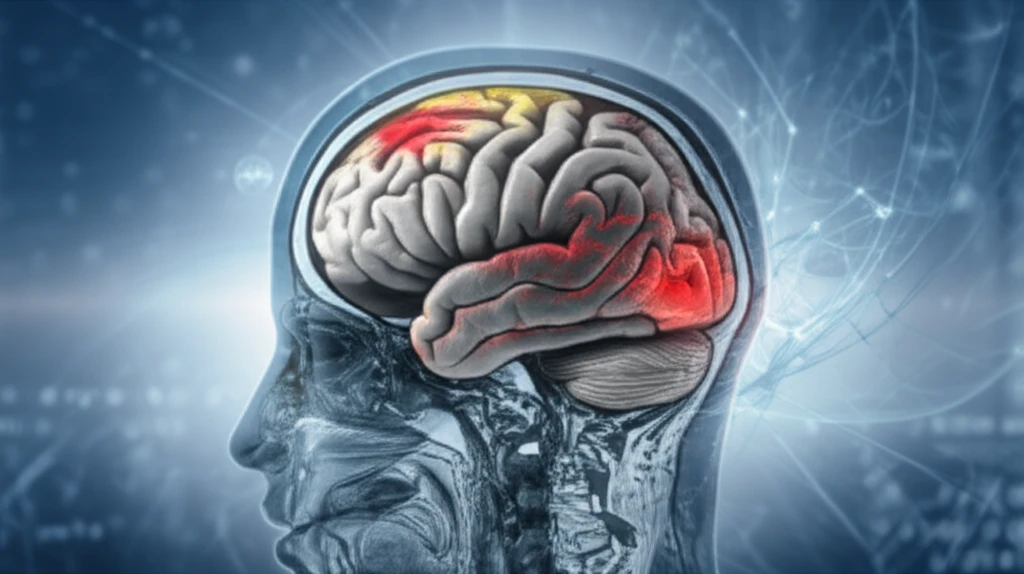

Traumatic brain injuries (TBIs) are a significant public health concern, affecting millions globally each year. While advancements in medical care have improved survival rates, understanding the long-term consequences of these injuries remains a critical challenge. Recent studies are shedding light on the intricate damage that occurs within the brain, specifically focusing on the role of grey matter and the subtle changes that occur over time.

Traditional methods often focus on visible damage, leaving much of the injury's complexity unseen. But what if we could see the invisible? Recent research is utilizing cutting-edge techniques, like Diffusion Tensor Imaging (DTI) and Diffusion Kurtosis Imaging (DKI), to peer deep into the brain's structure. These methods, combined with traditional histological analysis, offer a powerful new way to track injury progression and understand how the brain responds to trauma.

This groundbreaking work isn't just about new technologies; it's about hope. By understanding the fine details of how grey matter changes after injury, we can move closer to more accurate diagnoses, targeted treatments, and ultimately, better outcomes for those affected by TBIs. This article explores these exciting new frontiers in brain injury research, explaining the science and its potential impact.